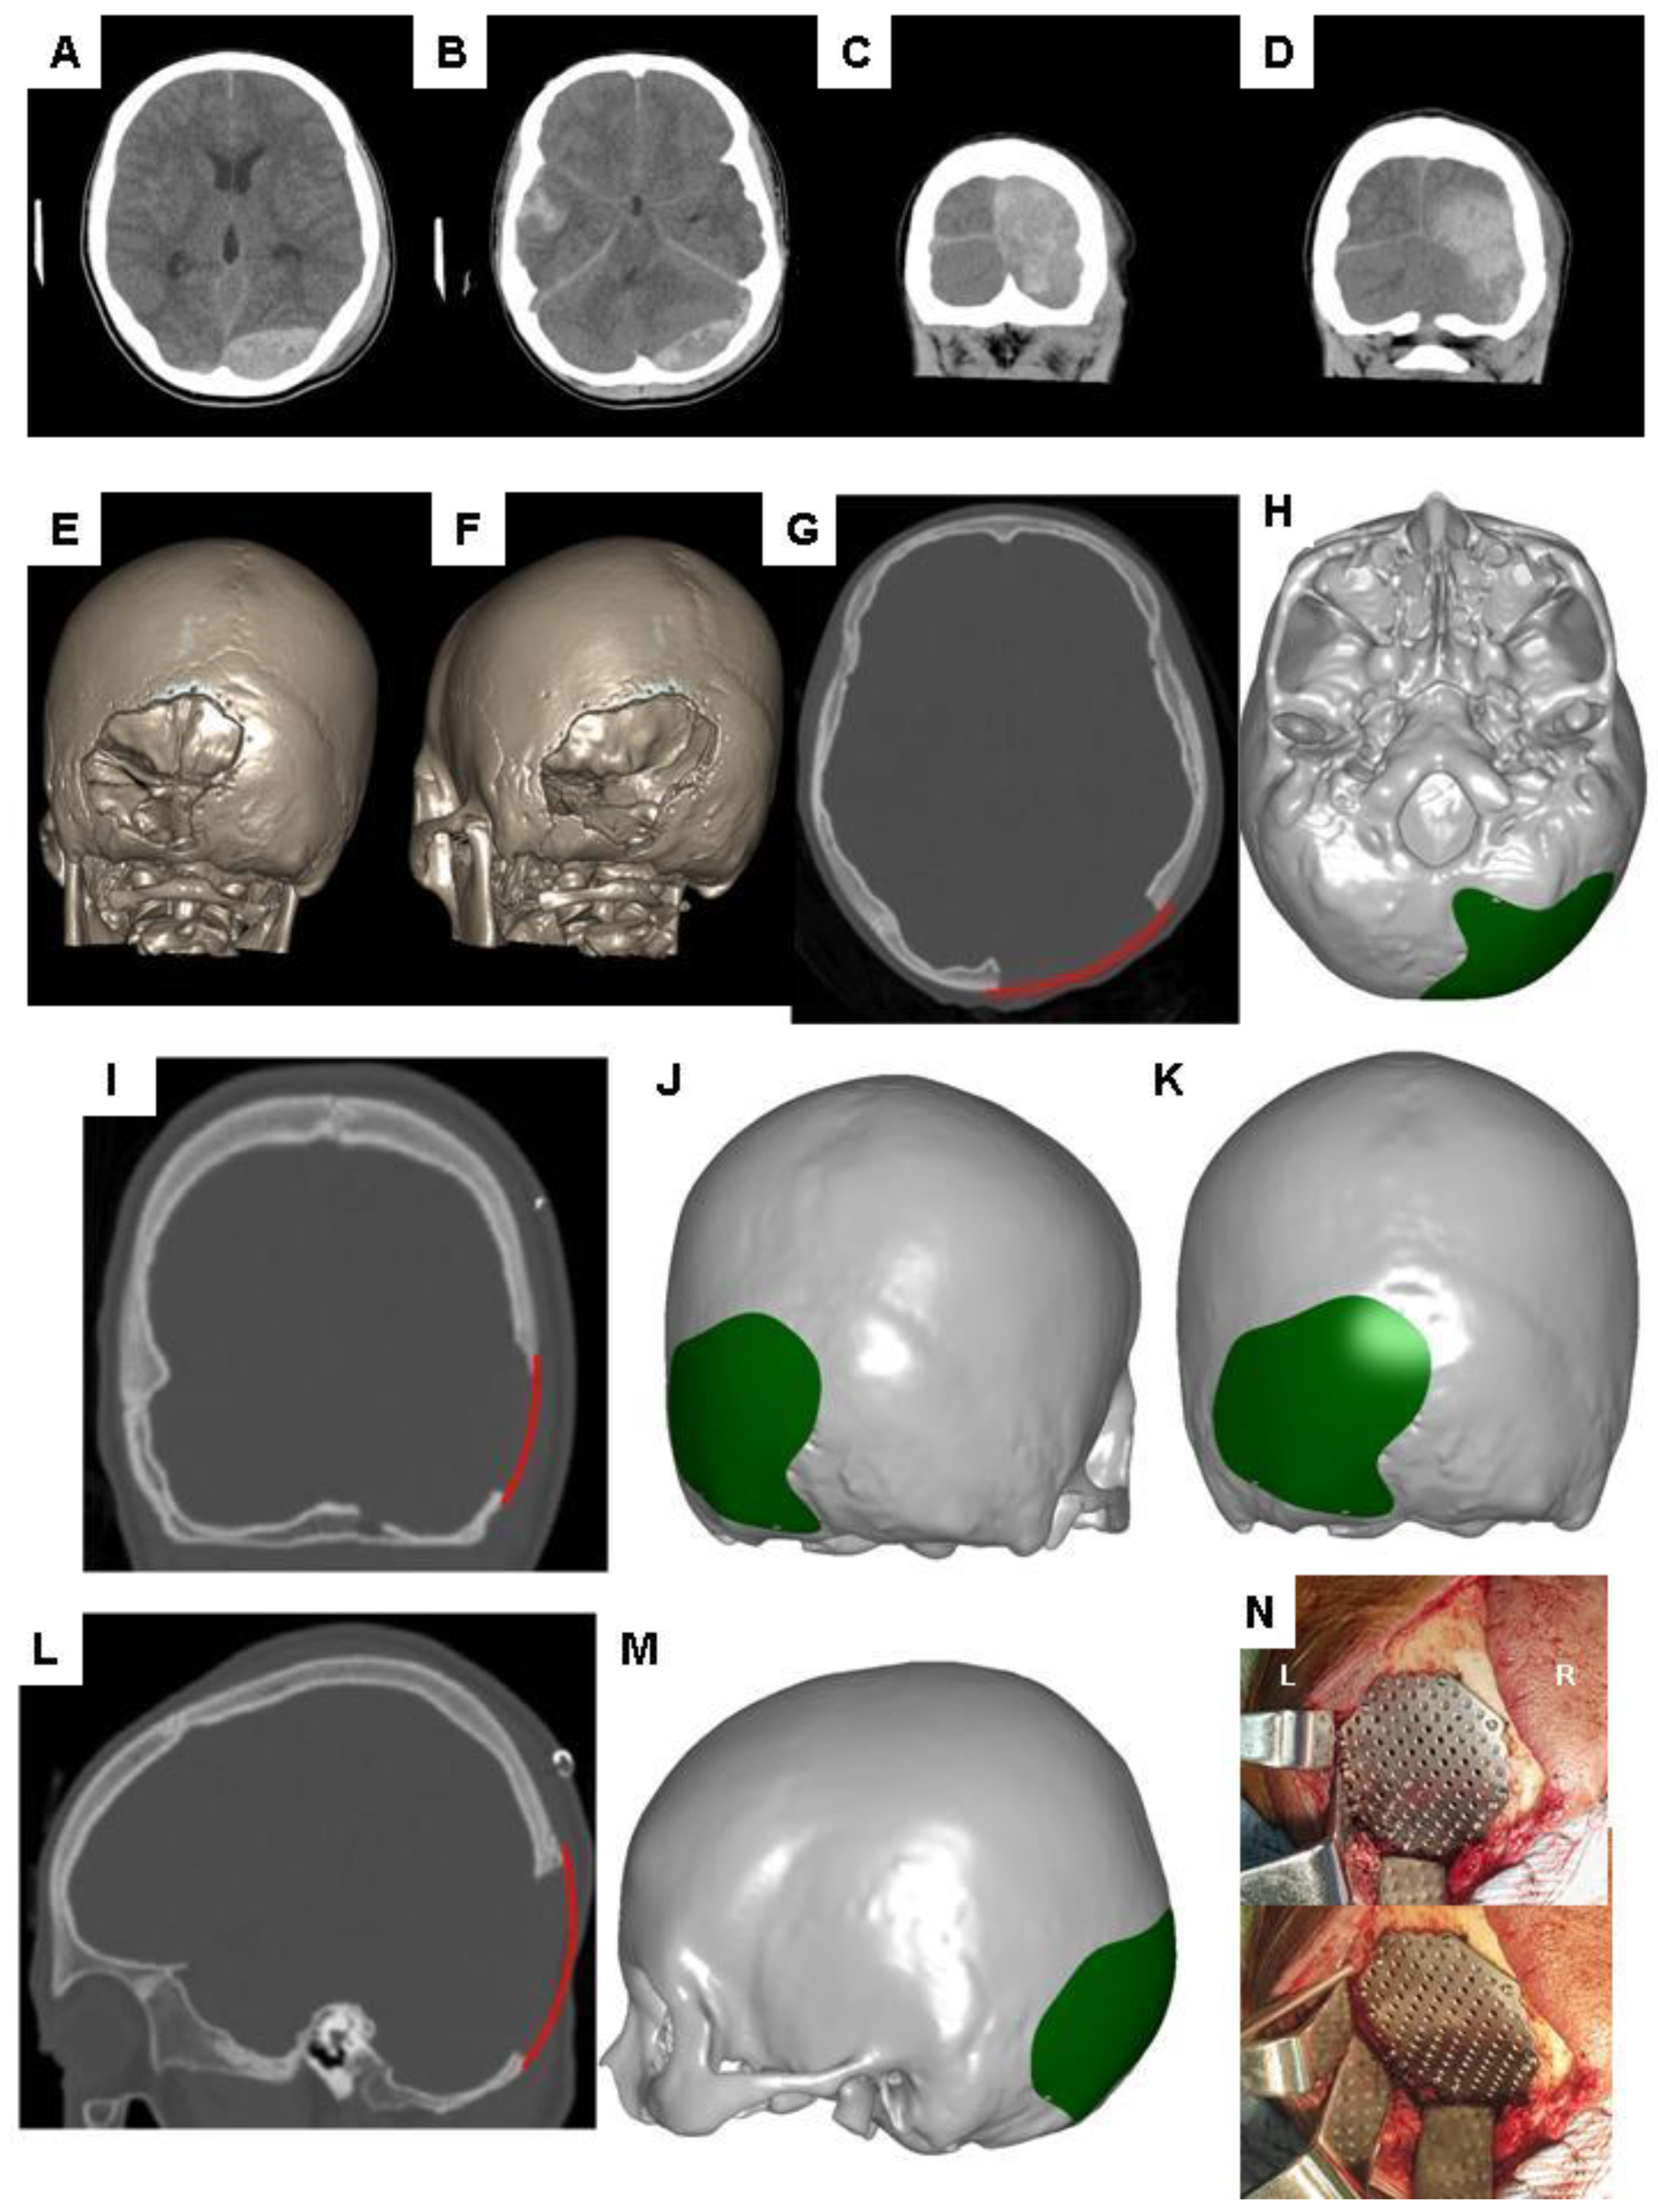

6. Brief Overview of the CAD Modeling Process for the Reconstruction of Cranial Defects

7. Demonstration of Editing the 2-D Images of Brain CT Scans Using Commercial Software

8. Brief Overview of CAM Processing for Reconstruction of Cranial Defects

10. Demonstration of Adjusting Contours for the Reconstruction of Skull Defects in CAD Modeling